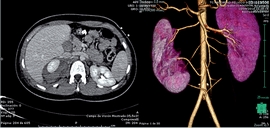

Al ingreso, hemoglobina de 7 g/dL; leucocitos 8420/mm3 (72.9% polimorfonucleares; 12.5% linfocitos) y 141.000/mm3 plaquetas. La coagulación, bioquímica, ácido láctico y gasometría sin alteraciones; con un péptido natriurético tipo B de 283.8 pg/mL. Una angioTac abdominal y pélvica mostró malformación de la vasculatura renal y hematoma retroperitoneal derecho sin signos de sangrado activo (Figura 1).